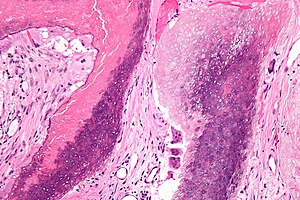

Pilomatricoma. H&E stain. | |

| LM | "ghost" cells, foreign body-type giant cells |

| LM DDx | squamous cell carcinoma, pilomatrix carcinoma, basal cell carcinoma, epidermal inclusion cyst, heterotopic ossification |

- Nodular circumscribed lower dermis/subcutaneous adipose lesion; thus, usu. surrounded by connective tissue.

- Sharpy demarcated island of cells.

- Calcification in 75%.

- Cells:[5]

- Basaloid epithelial cells - have prominent nucleoli.

- Anucleate squamous cells ("ghost cells").

- Giant cell foreign body type granulomas (form in reaction to keratin).